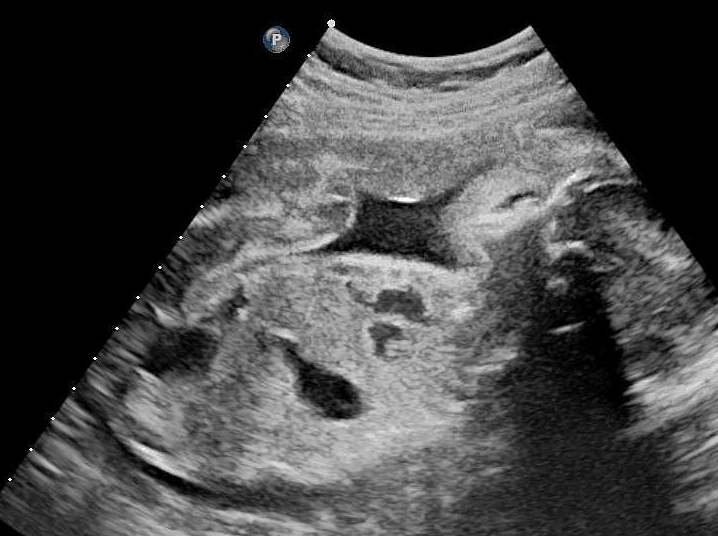

胎盘前壁和后壁对顺产的影响并不大顺产的关键因素包括胎位胎儿大小宫颈条件等,而胎盘的位置通常不会成为顺产的障碍无论胎盘附着于子宫前壁还是后壁,只要胎盘下缘不低于胎儿先露部,一般都可以顺利进行顺产胎盘的位置是在早期妊娠时确定的如果妊娠囊在孕早期着床于子宫前壁,那么胎盘就会附着;与前置胎盘的区别需要特别注意的是,胎盘前壁并不等同于前置胎盘前置胎盘是指胎盘位于子宫下段,低于胎儿先露部,甚至完全覆盖或部分覆盖子宫内口前置胎盘有导致产前产时或产后大出血的风险,需要及时就医并进行相应的处理对顺产的影响胎盘前壁并不会影响顺产能否顺产主要取决于胎儿的大小。

前置胎盘大多数不能自然分娩,尤其是中央型前置胎盘如果是前壁胎盘,正常位置的胎盘位于子宫前壁,对于分娩没有任何影响顺产是否生得顺利,主要取决于产力产道和胎儿,正常有效的子宫收缩,很好正常的范围的骨盆以及不是很大的正常胎位的胎儿,都是顺产需要的条件;胎盘位置与顺产胎盘附着在子宫前壁或后壁,只要胎盘的最下缘不低于先露部,都可以进行顺产这是因为胎盘的位置并不会阻碍产道的开放和胎儿的下降胎盘附着位置的正常性胎盘附着于子宫前壁后壁和侧壁都是正常的情况这些位置的选择取决于孕早期时妊娠囊着床在子宫的具体位置,是自然生理过程的一。

顺产时女性胎盘前壁好还是后壁好,都不会影响到顺产的过程胎盘不管是附着在子宫前壁,还是后壁上,只要胎盘的最下缘不低于先露部,都可以进行顺产胎盘附着于子宫前壁后壁和侧壁是正常的情况,而胎位的具体位置,取决于在孕早期时妊娠囊着床在子宫的具体位置如果孕初期时,妊娠囊着床在女性子宫;胎盘前置是否可以顺产,需要根据具体情况来判断胎盘前壁与前置胎盘的区别胎盘前壁是指胎盘附着在子宫的前壁,这是正常的胎盘位置之一,不影响顺产,也没有出血风险胎盘前置是指孕28周后胎盘位置低于胎儿头部先露出的位置,这是一种异常情况,可能影响分娩方式胎盘前置的分娩方式如果孕28周后,胎盘完全覆盖宫颈内口,通常会选择剖宫产终止妊娠。

怀孕子宫前壁不影响顺产能否顺产主要取决于以下几个因素胎儿大小如果胎儿长得过大,可能会增加顺产的难度胎位正常的胎位是胎儿头部朝下,这种胎位更利于顺产脐带情况如果脐带绕颈等,可能会影响到顺产而胎盘位于子宫前壁是正常的胎盘位置,与能否顺产没有直接关系此外,为了帮助孕妇更好地;顺产时前壁好还是后壁好,应该指胎盘前壁好还是后壁好胎盘无论是附着于子宫的前壁还是后壁,只要胎盘的最下缘不低于先露部都是一样的,并不影响顺产的几率胎盘附着于子宫的前壁后壁侧壁都是正常的,取决于在妊娠早期妊娠囊着床在子宫的位置如果妊娠囊着床在子宫前壁,胎盘就附着于子宫前。